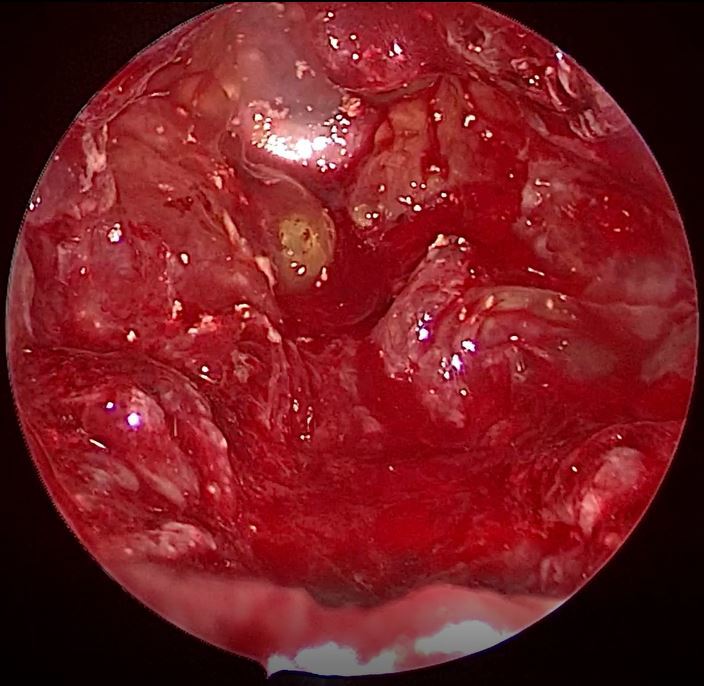

分享一例鞍区脑膜瘤手术病例原创

图片尺寸4032x3024